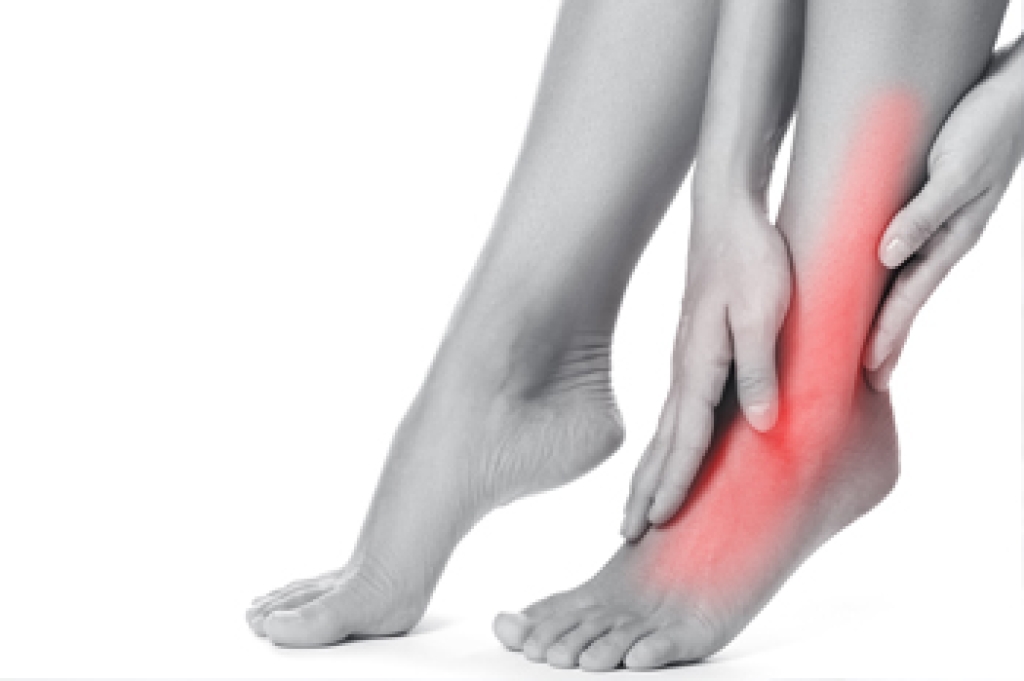

Swollen feet occur when excess fluid builds up in the tissues of the lower extremities. This condition, termed edema, can result from standing or sitting for long periods but may also indicate underlying health concerns such as heart disease, kidney disease, liver disease, or chronic venous insufficiency. Swelling may cause discomfort, heaviness, or visible puffiness in the feet and ankles. A podiatrist can help determine the cause through a thorough evaluation and recommend treatment, such as compression therapy and circulation improvement. If your feet are consistently swollen, it is suggested that you consult a podiatrist who can provide an accurate diagnosis and offer effective relief tips.

Many patients elevate their feet to help relieve the swelling and this is generally a temporary remedy. When a podiatrist is consulted the reason behind the swelling can be uncovered and subsequently treated.